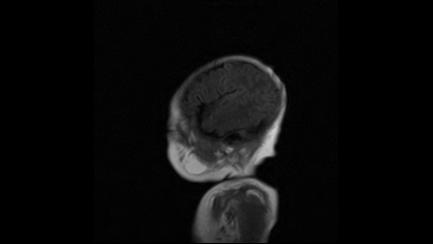

标题: PED3413:患儿女6天体检

缺血缺氧性脑病

6天为新生儿,髓鞘发育正常;左侧颞顶叶蛛网膜下腔增宽,请结合临床。

1。缺血缺氧性脑病2。左侧颞顶叶外部性脑积水,可观察

半卵圆中心上方层上可见对和乐大脑皮质t1高信号,考虑有hie可能,不知有何症状,建议加做dwi及复查

符合缺氧缺血性脑病影像表现。